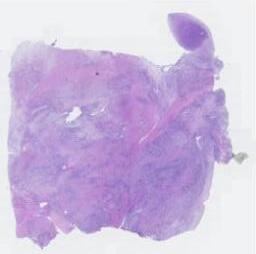

临床资料: 女,33岁,发现宫腔占位1年余。现病史:平素月经规律,经期5天,周期30天,量中等,色暗红,偶有痛经,末次月经:2023-06-02;1年前在郑州市体检中心行腹部超声检查发现:宫腔占位(未见报告单);1月前至我院门诊复查三维阴超示:【实时三维阴式超声检查】子宫:宫体大小约50X46X54mm,形态正常,轮廓清晰,肌壁回声均匀。(节育环未见)宫腔内可见范围约39×23×22mm不均匀高回声,局部与子宫壁分界不清,似侵入后壁肌层内,形态规则,内可见多个点状强回声,CDFI:内可见杂乱、丰富血流信号,RI:0.45。双侧卵巢大小正常。盆腔:未探及明显液性暗区;超声诊断意见:宫腔内不均匀高回声(息肉样变?内膜Ca?建议宫腔镜进一步检查)。既往史:2019年在我院行腹腔镜下左侧卵巢囊肿剥除术+卵巢复位术+修补术+左侧输卵管系膜囊肿剥除术+肠粘连松解术+屏障物置入术。